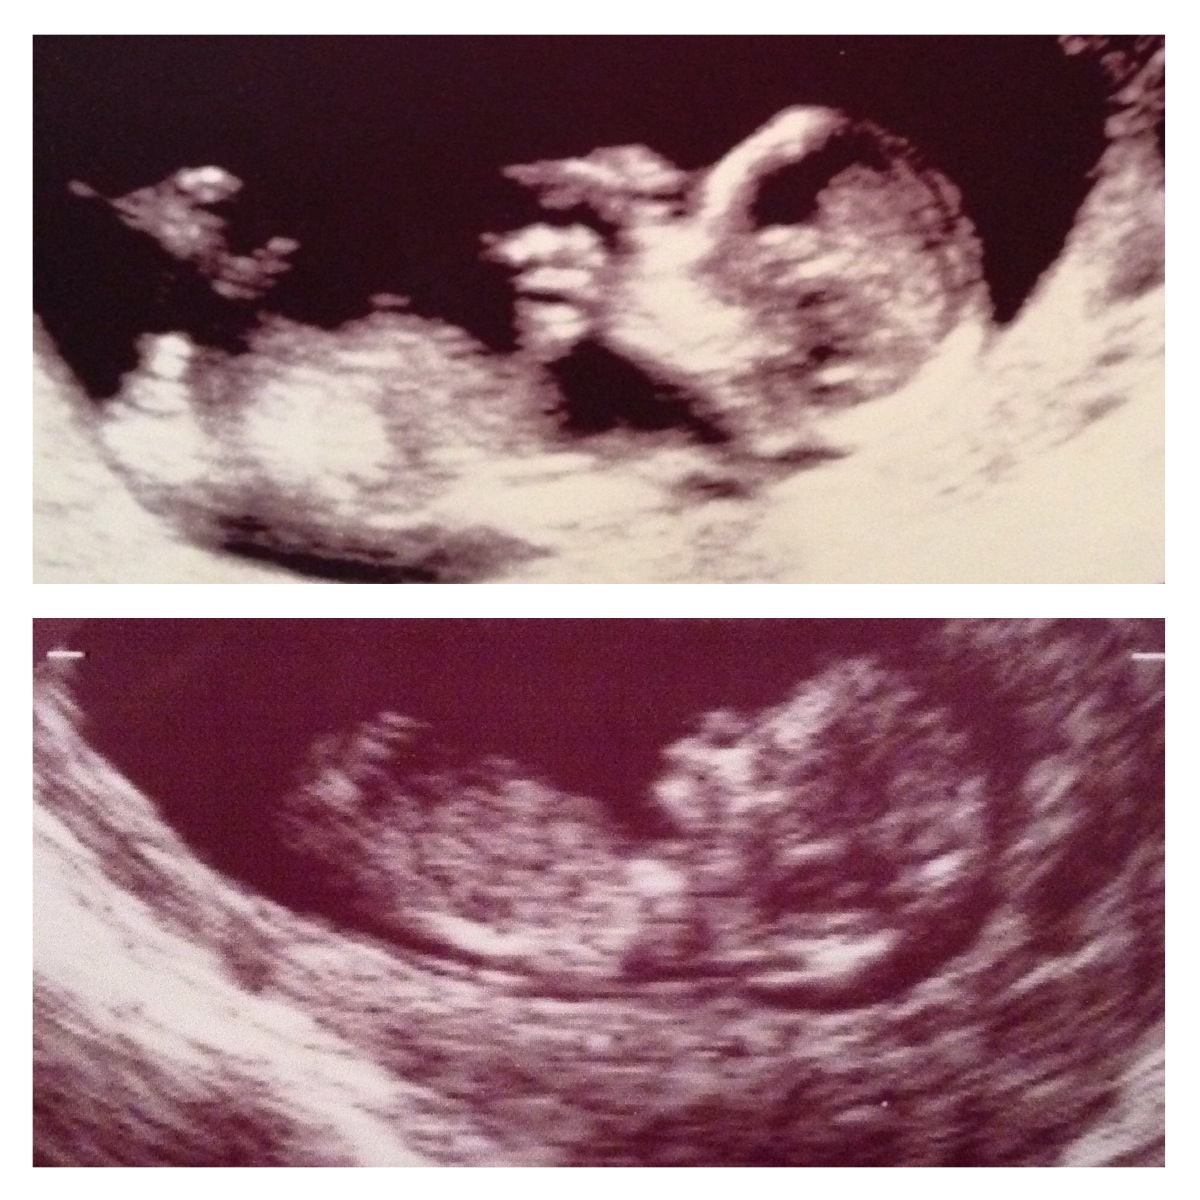

Not sure if this helps but I'm posting a pic of my son's ultrasound at 12 weeks on top of my baby #2's 12 week ultrasound. You can see from my son's top pic his obvious boy nub and his skull seems it's larger than my baby 2.

I am really hoping for a girl so not sure if I'm imagining the smaller skull.